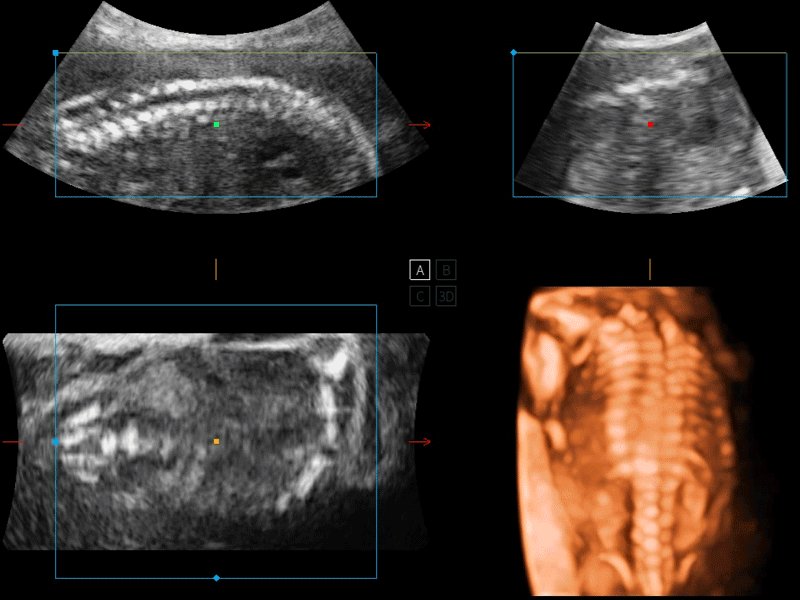

S-Live 高分辨率容积成像

通过仿真成像技术对3D/4D立体数据进行渲染,多种初始光源位置可选,并支持轨迹球360°光源位置自由调节,清晰显示不同方位容积图像细节。

S-Fetus 产科扫查助手

S-Fetus基于大数据深度学习算法,能够帮助您在产前筛查过程中智能识别胎儿标准切面、自动测量并录入报告。一个按键,即可智能、精准、高效地获取胎儿生理指标,极大简化您的产科检查操作。

临床图像